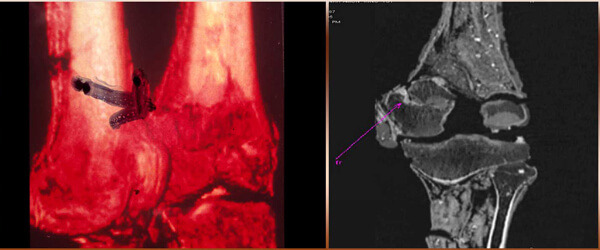

원한 없는 저주는 없기에, 투탕카멘의 저주인 ‘파라오의 저주’는 실체를 해부할 필요가 있다. 투탕카멘 무덤의 발굴 당시 미라의 X선을 촬영한 결과, 머리에 둔기를 맞은 듯한 두개골 골절이 발견되어 투탕카멘이 암살을 당했다는 설이 설득력 있게 주장되었다. 실제 고대 이집트 역사에 따르면 투탕카멘이 죽은 뒤로 의문투성이의 왕위 계승이 일어나기도 했다. 이를 통해 일부 고고학자들은 투탕카멘의 죽음을 ‘왕위를 노린 자에 의한 살인’으로 정의하고 있다.

투탕카멘이 살해당한 것이 아니라는 반박설도 유력하다. 투탕카멘의 미라 X선 촬영 이후 밝혀진 또 다른 사실에 의하면, 투탕카멘은 살해로 인해 죽은 것이 아닌 다리의 심각한 골절이 상처로 덧나 죽은 것이라는 주장이 있다. 항생제라는 개념이 없었던 고대 이집트 당시에는 이러한 상처가 곪고 덧나 죽는 경우가 상당히 많았다는 설이 있기 때문이다. 한편으로는 투탕카멘의 부친이 유전적 기형 의혹을 받고 있어 유전병으로 인해 오래 재위하지 못하고 병사했다는 시각도 나온다.